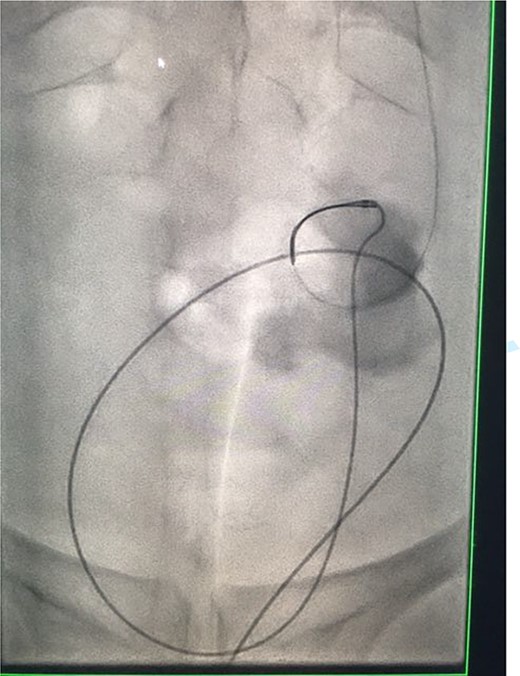

A catheter-guidewire exchange was performed to upsize the guidewire to a 0.035-inch stiff guidewire. An 8-Fr, 26-cm nephroureteric stent was inserted over the guidewire in an antegrade manner (Fig. 8). The stent was left to free external drainage. The patient was transferred back to the ward and discharged home the following day. Trial without bladder catheter was successfully undertaken 1 week post-procedure.

Fluoroscopic images demonstrating the successfully re-connected right ureter with a nephroureteric stent in situ.